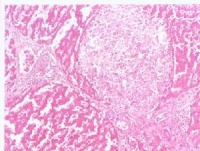

饮食过量或饮食不当(尤其是狂饮暴食)是引起急性胃扩张的最常见病因。短时间内大量进食使胃突然过度充盈、胃壁肌肉受到过度的牵拉而发生反射性麻痹,食物积聚于胃内,胃持续扩大。胃扩大后,胃粘膜的表面积剧增,胃壁受压,胃的血循环受阻,加之食物的发酵引起的胃粘膜炎症,使胃粘膜有大量液体渗出胃窦的扩张和胃内容物的刺激使胃窦分泌的胃泌素增多,刺激了胃液的分泌;小肠受扩大的胃的推移而使肠系膜受到牵拉,一方面影响腹腔神经丛而加重胃的麻痹,另一方面十二指肠横部受到肠系膜上动脉的压迫及空肠上部受到牵拉而出现梗阻,加上幽门松驰等因素,使十二指肠液的返流增多;另外由于扩大后胃与食管角度的改变,使胃内容物包括气体难于经食道排出,这些因素互为因果,形成恶性循环,终使胃呈急剧的、进行性的扩大,形成急性胃扩张。如病情继续发展,胃壁的血循环状况将进一步恶化,可出现血性渗出,最后可出现胃壁的坏死甚至穿孔

急性胃扩张可因胃壁坏死发生急性胃穿孔和急性腹膜炎